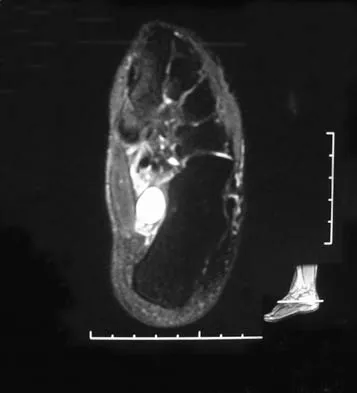

A 37-year-old woman has had intermittent paresthesias and numbness in the plantar foot for the past 6 months. She reports that the symptoms are worse with activity, and the paresthesias are beginning to awaken her at night. MRI scans are shown in Figures 6a and 6b. What is the most likely diagnosis?

Explanation

The symptoms are consistent with tarsal tunnel syndrome. Ganglion cysts are a well-known cause of tarsal tunnel syndrome. The MRI scans show a high intensity, well-circumscribed mass in the tarsal tunnel that is consistent with a fluid-filled cyst. Patients usually respond well to excision of the ganglion and resolution of the tarsal tunnel symptoms. The surrounding fat is a different signal intensity on the MRI scans, which rules out a lipoma. Synovial cell sarcoma has a heterogeneous appearance on an MRI scan. Metastatic tumors are most commonly found in the osseous structures of the foot, not the soft tissues. Rozbruch SR, Chang V, Bohne WH, et al: Ganglion cysts of the lower extremity: An analysis of 54 cases and review of the literature. Orthopedics 1998;21:141-148. Llauger J, Palmer J, Monill JM, et al: MR imaging of benign soft-tissue masses of the foot and ankle. Radiographics 1998;18:1481-1498.